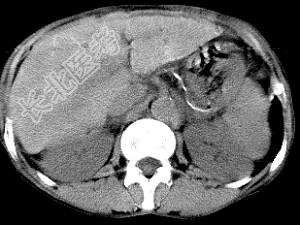

- 单项选择题男,40岁有血吸虫感染史, 腹胀不适,食欲减退, CT扫描所见如图,最可能诊断为 ( )

A、脂肪肝

B、肝炎后肝硬化

C、血吸虫后肝硬化

D、酒精性肝硬化

E、胆汁性肝硬化